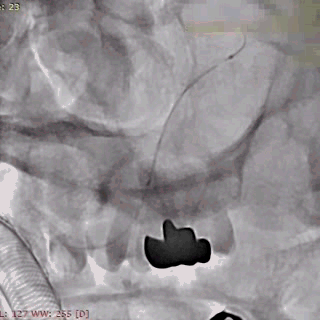

浦奔放教授病例分享二:右侧椎动脉夹层动脉瘤

患者:男性,50岁。

主诉:患者自诉于两周前无明显诱因出现头痛,以右侧枕部胀痛为主,休息后缓解。

颈部CTA提示:右侧V4近段及中上段、右侧V4中上段管腔中-重度狭窄,动脉夹层可能。

左侧椎动脉:

右侧椎动脉(劣势):

左侧椎动脉劣势,颅内段纤细;右侧V4段夹层,血管狭窄。

载瘤动脉远端血管直径:1.50mm

载瘤动脉近端血管直径:1.83mm

2mm*20mm 强易达(Choydar)血流导向密网支架

3mm*25mm 强易达(Choydar)血流导向密网支架